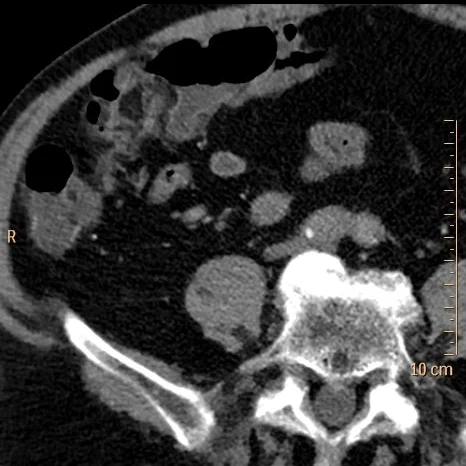

Conventional CT with filling defect in right ureter (yellow circle)